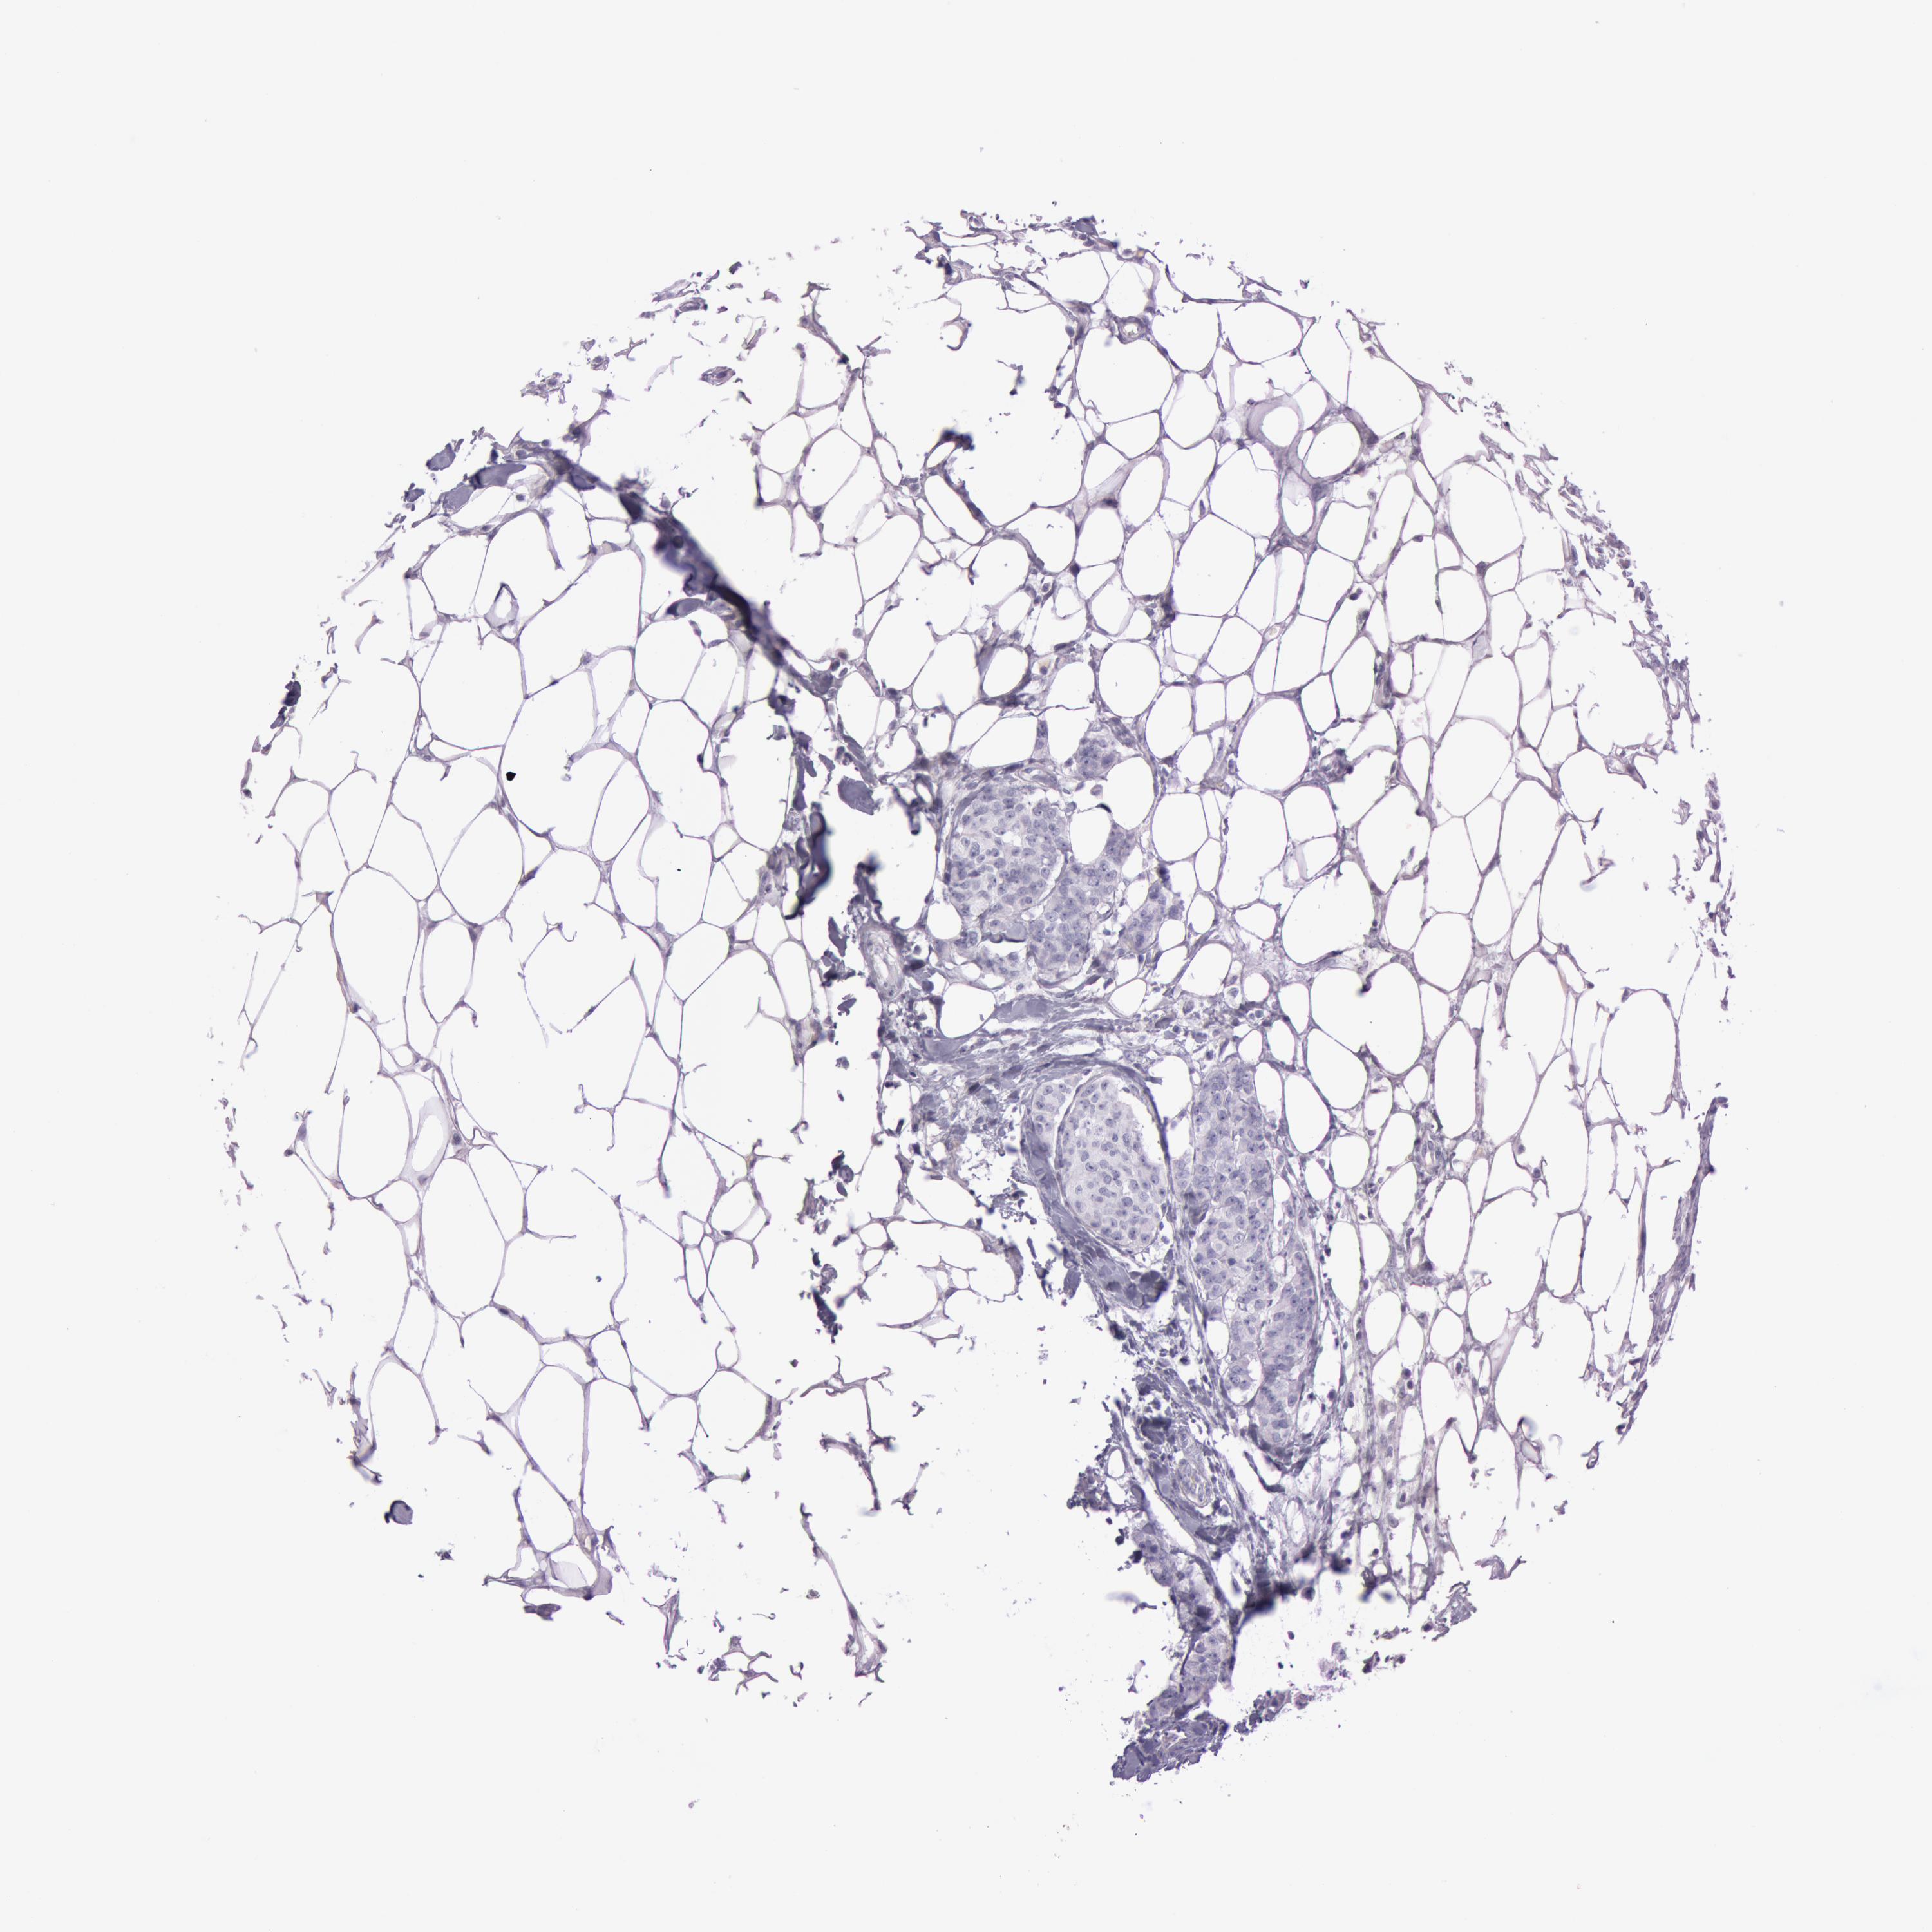

Breast cancer

Human cancer